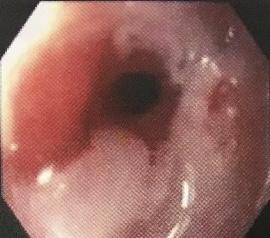

Estenosis esofágica

డా. గన్నవరపు నరసింహమూర్తి, CC0, vía Wikimedia Commons.

Graduación endoscópica de la esofagitis

Se suele utilizar el sistema de clasificación Savary-Miller:5 Grado 1: erosiones únicas o múltiples en un solo pliegue. Las erosiones pueden ser exudativas o eritematosas. Grado 2: erosiones múltiples que afectan a múltiples pliegues. Las erosiones pueden ser confluentes. Grado 3: erosiones circunferenciales múltiples. Grado 4: úlcera, estenosis o acortamiento esofágico. Grado 5: Epitelio de Barrett. Metaplasia columnar en forma de extensiones circulares o no circulares (islas o lenguas). Grado A: una o más roturas de la mucosa de no más de 5 mm, ninguna de las cuales se extiende entre la parte superior de los pliegues de la mucosa. Grado B: una o más roturas de la mucosa de más de 5 mm de longitud, ninguna de las cuales se extiende entre la parte superior de dos pliegues mucosos. Grade C: mucosal breaks that extend between the tops of two or more mucosal folds but which involve <75% of the mucosal circumference. Grado D: roturas de la mucosa que afectan a ≥75% de la circunferencia de la mucosa. |